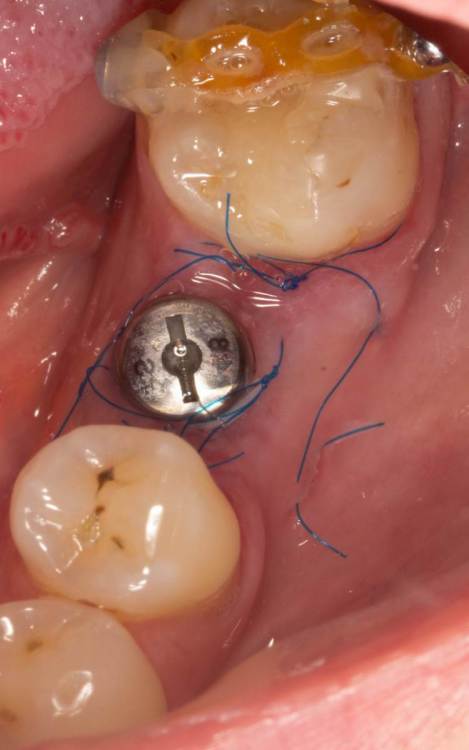

Женька Опубликовано 24 июня, 2023 Поделиться Опубликовано 24 июня, 2023 Собственно похожий случай. Разница лишь в том, что тут заглушка просвечивала. Предоп фоток, к сожалению, нет. 3.6*08мм, тк очень тонко было. Торк при установке потерял. Около 5 примерно был. В данном случае решил сст только вестибулярно положить. p.s. да, налёта много. Пациентка сестра моей одногруппницы, и чистит зубы только у сестры... при встрече я не думал, что чистки давно не было. Косяк, не отрицаю. Фотку со швами забыл сделать. Сделаем на снятии. Ссылка на комментарий

Женька Опубликовано 26 июня, 2023 Автор Поделиться Опубликовано 26 июня, 2023 @Fin корея. В отсутствии десны язычно. Кмк, эти проблемы я создал собственноручно. Неправильным разрезом и ушиванием, кмк опять же. @bakagaidzin в соседней теме про тл вообще сказали, что БЛ) и зачем так утопил Ссылка на комментарий

Fin Опубликовано 27 июня, 2023 Поделиться Опубликовано 27 июня, 2023 12 часов назад, Женька сказал: @Fin корея. В отсутствии десны язычно. Кмк, эти проблемы я создал собственноручно. Неправильным разрезом и ушиванием, кмк опять же. @bakagaidzin в соседней теме про тл вообще сказали, что БЛ) и зачем так утопил По фото не кажется что там совсем все плохо,2 мм прикреплении вроде есть. Может ССТ язычно? Ссылка на комментарий

Женька Опубликовано 27 июня, 2023 Автор Поделиться Опубликовано 27 июня, 2023 Тут не стал сст сажать... тк при расщеплении язычно ниже платформы перфорировал лоскут( Подумал, что питания от перекинутого лоскута будет мало для сст. В первой теме-да, сст с двух сторон. Ссылка на комментарий